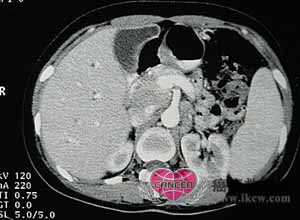

2.肝脾肿大

脾肿大常见(40%),轻至中度肿大,晚期可达盆腔,偶可发生脾梗死或脾破裂。肝肿大(10%)程度不如脾脏,当明显肿大伴肝功能损害,常提示晚期病例。